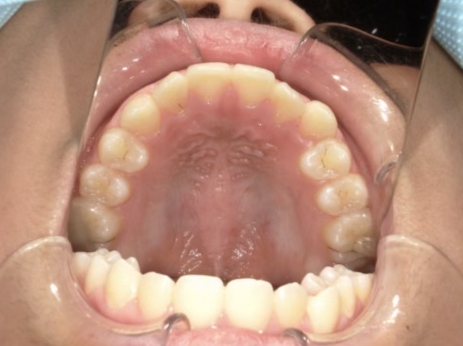

治療中⑤ 小5:10y11m

モノブロック装置継続中、左上3が八重歯で萌出